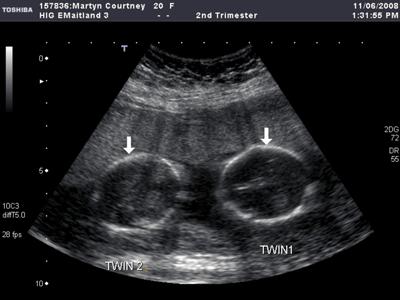

Всього лише кілька десятиліть тому, майбутня мати могла дізнатися про появу на світ одразу двох діток тільки в момент пологів. Сьогодні, коли настав століття, що стрімко розвиваються, нових технологій, за допомогою ультразвукового дослідження, дізнаються про це вже на початкових термінах вагітності. Приблизно починаючи з десятого тижня вагітності, лікар може визначити за допомогою апарату УЗД наявність двох плодів, які розвиваються одночасно.

(3D УЗД двійні)